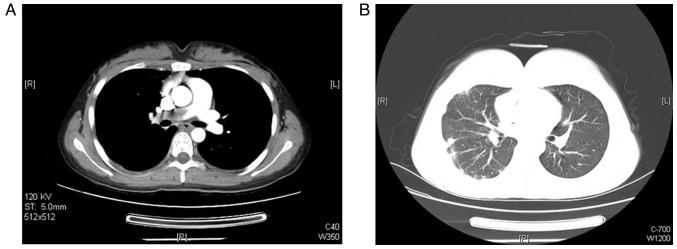

Pulmonary embolism (PE) caused by malignant tumor is not uncommon, but pulmonary artery with choriocarcinoma is rare and difficult to timely diagnose and effectively treat. To the best of our knowledge, there are only 15 cases reported at present in the literature that present variable clinical characteristics and prognosis. In the current study reports a 21-year-old female with a history of chest pain and slight fever for 4 months who was treated as a case of pneumonia. Owing to the recurrence of the symptoms, a contrast-enhanced chest computer tomography scan was performed on the patient, which revealed complete occlusion of the right pulmonary artery. The patient was diagnosed to have pulmonary embolism (PE). However, no abnormalities were observed in D-dimer value, tumor antigen testing or ultrasonography. Positron emission tomography/computed tomography (PET/CT) was performed, which revealed the abnormal hypermetabolic lesion of the right pulmonary artery. Following the laboratory report of a significantly elevated human chorionic gonadotropin β-subunit level combined with characteristic appearance of PET-CT, the diagnosis of primary pulmonary artery with choriocarcinoma was established based on guidelines of the European Society for Medical Oncology and the criteria formulated by the International Federation of Gynecology and Obstetrics. The patient underwent chemotherapy and responded well to the treatment. Although rare, choriocarcinoma should be considered for any fertile women who presents with a massive PE. These findings emphasize the importance of the early diagnosis and treatment of this disease.

恶性肿瘤所致肺栓塞(PE)并不少见,但绒毛膜癌累及肺动脉者罕见,且难以及时诊断和有效治疗。据我们所知,目前文献中仅报道了15例,其临床特征和预后各异。在本研究中,报告了一名21岁女性,有胸痛和低热4个月病史,最初按肺炎治疗。因症状复发,对该患者进行了胸部增强计算机断层扫描,结果显示右肺动脉完全闭塞。患者被诊断为肺栓塞(PE)。然而,D - 二聚体值、肿瘤抗原检测或超声检查均未发现异常。进行了正电子发射断层扫描/计算机断层扫描(PET/CT),显示右肺动脉有异常高代谢病变。结合实验室报告显示人绒毛膜促性腺激素β亚单位水平显著升高以及PET - CT的特征性表现,根据欧洲医学肿瘤学会指南和国际妇产科联合会制定的标准,确诊为原发性肺动脉绒毛膜癌。该患者接受了化疗,治疗反应良好。尽管罕见,但对于任何出现大面积肺栓塞的育龄女性都应考虑绒毛膜癌的可能。这些发现强调了该病早期诊断和治疗的重要性。